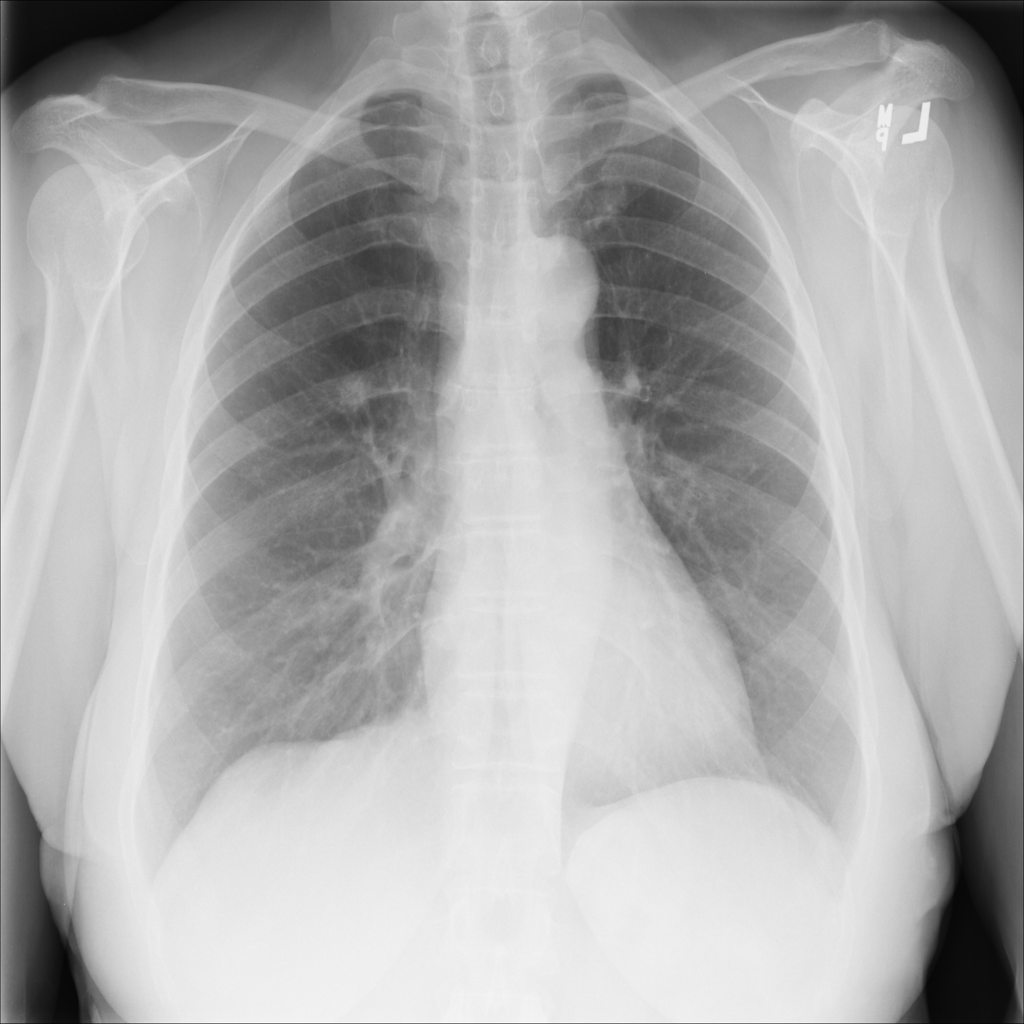

Mass

A mass is a larger focal opacity or lesion seen on the image. It is a descriptive finding that can have several causes and usually needs more imaging or clinical context to characterize.

PAT-C0E5 · IMG-001Mass

PAT-C0E5 · IMG-001

PA